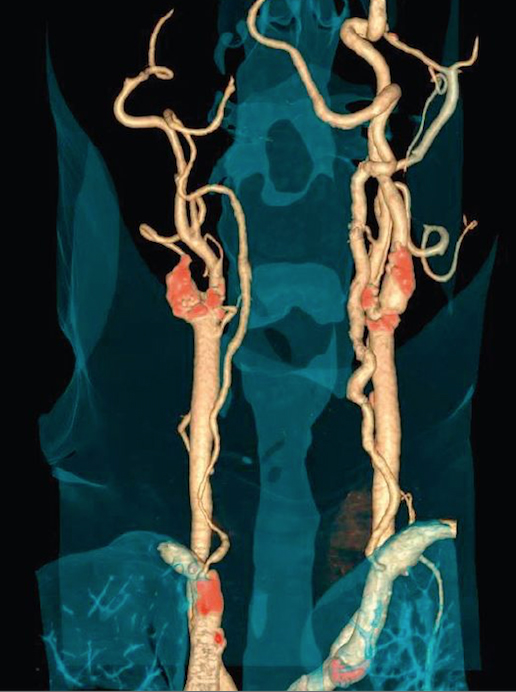

suspektnom koronarnom bolesti, umjerenim do visokim rizikom ali s atipičnim anginoznim simptomima neodredjenim rezultatom ergometrije ili drugog stress testa koji nisu u mogućnosti da urade stress-test neuobičajenim simptomim koronarne bolesti ali niskog do umjerenog rizika. kompleksnim urodjenim srčanim manama uključujući koronarne anomalije, anomalije velikih krvnih žila, srčanih šupljina i zalistaka. s akutnim bolom u grudima, niskim do umjerenim rizikom koronarne bolesti, bez promjena na EKG-u i negativnim biohumoralnim sindromom evaluacija koronarnog statusa kod pacijenata s nedavnim početkom popuštanja srca nejasne etiologije neinvazivni maping koronarnog stabla uključujući arterije mamarije interne prije ponavljanja hirurške revaskularizacije